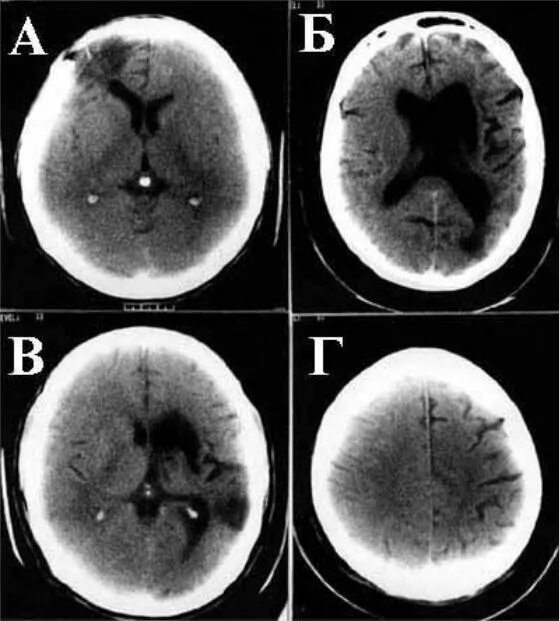

Субарахноидальное пространство лобных долей